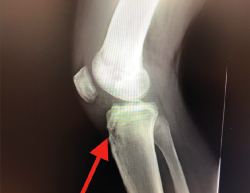

Un diagnóstico y una planificación correctos son fundamentales. En caso de rotura de plastia del LCA (Figura 3), se hace obligatoria, además de una detallada exploración, un correcto estudio radiológico completo que incluya radiología convencional y resonancia magnética (RM) –estudio de lesiones acompañantes o degeneración previa–. En ocasiones en donde la anamnesis/exploración lo justifique, pueden ser también necesarias telemetrías de extremidades inferiores, radiología forzadas (si existiera inestabilidad mediolateral) o tomografía axial computarizada (TAC) –valoración de la posición y la calidad de los túneles–.

Figura 3. Rotura de la plastia del ligamento cruzado anterior.